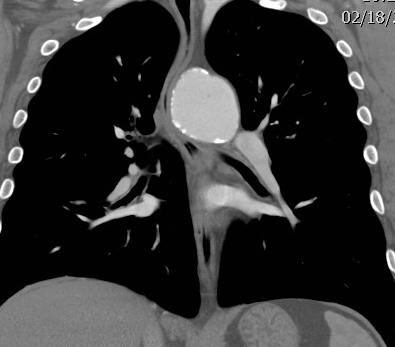

Gallery Blunt Chest Trauma Tr Aortic Injury Chronic TAI CT coronal

Chronic TAI CT coronal